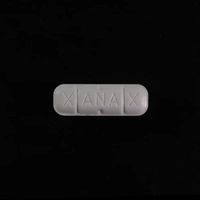

Database of Ecstasy pill reports contains lab and user data. Test results are warnings. No substance is 100% safe. Test it before you ingest it. Get a test kit.

Dislcaimer: The information provided on this page is not intended to promote drug use. Many of the substances mentioned are illegal under domestic and international law and possession of these substances is punishable by law. Never assume that a substance is safe. Ecstasy pills (extasy, XTC, molly) are expected to contain MDMA but concentration, purity and adulteration vary greatly, even if aquired from the same source or if bear seemingly the same characteristics. Chemical Safety sp. z o.o. strongly advises against the use of any psychoactive substance – legal or illegal. Consuming psychoactive substances is always an avoidable risk to your health.